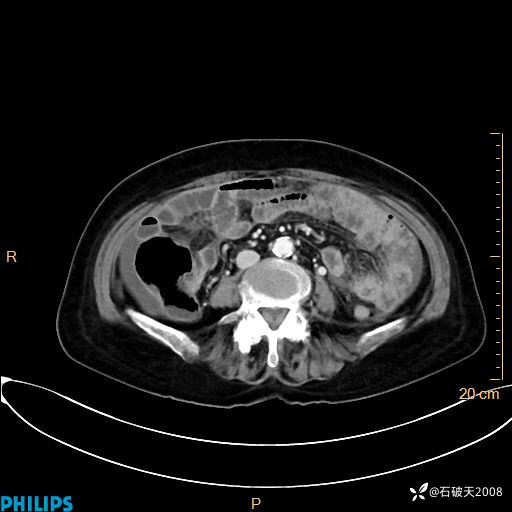

静脉期